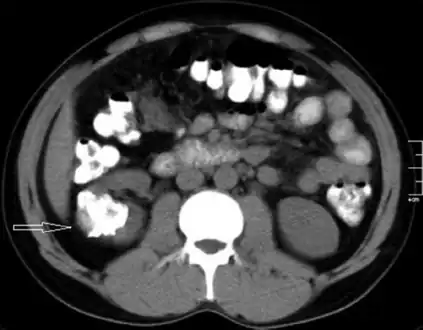

Left flank pain and gross hematuria diagnosed with renal medullary fibroma